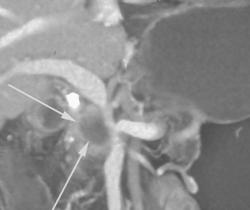

Cancer of the Pancreas Invading the Superior Mesenteric Vein (SMV)